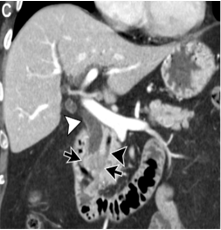

- A. Circumferential irregular submucosal wall thickening noted in D2 and D3 segment of duodenum causing luminal narrowing.

- B. Few hypoenhancing areas within the medial wall of duodenum. Uncinate process of pancreas appears oedematous.

- C. Contrast is seen passing from the duodenum into the jejunum. No contrast leakage noted.